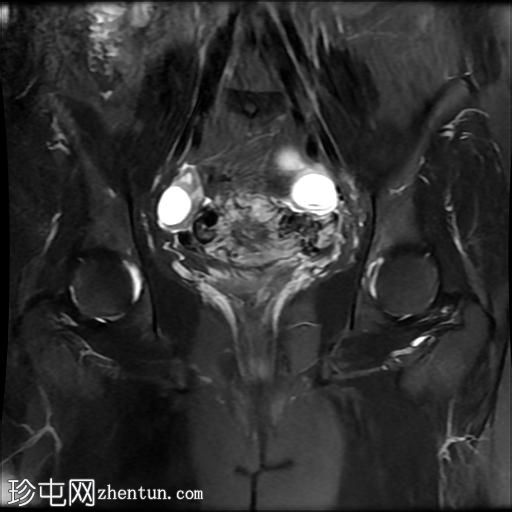

冠状位T2加权像

脂肪抑制像

盆腔MRI显示双侧子宫旁多条迂曲静脉,自子宫肌层延伸至盆腔。

此外,左侧附件可见两个充满液体的单纯性囊肿,大小分别约为31 mm和32 mm;右侧附件可见一个卵泡囊肿,大小约为19 mm。

影像学特征符合盆腔充血综合征的诊断,患者为35岁女性,有慢性盆腔疼痛和痛经病史。